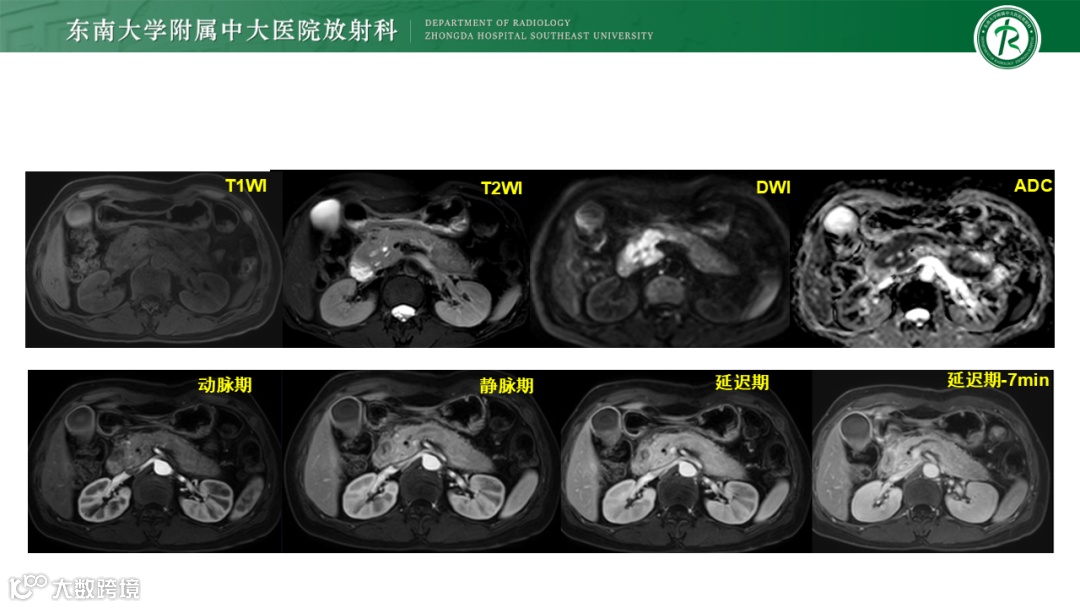

病例1:胰腺导管腺癌-高中分化

病例2:1)炎性肌纤维母细胞肿瘤 2)局限性非肿瘤性病变,如IgG4相关性硬化性疾病 3)韧带样纤维瘤病待排

病例3:胰腺导管腺癌

病例4:IgG4自身免疫性胰腺炎